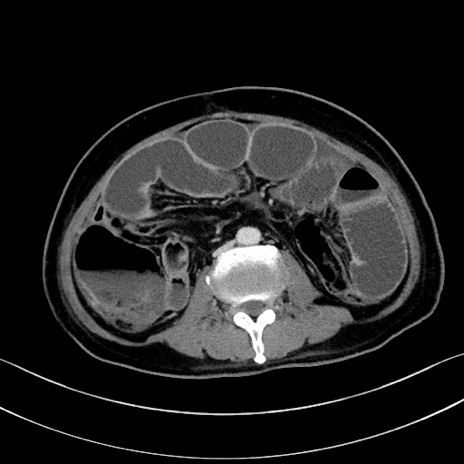

冠状断像

【症例】60歳代男性

【主訴】嘔吐

【現病歴】胃癌にて胃全摘後。食思不振が悪化し、夜中に嘔吐することがある。

【既往歴】胃癌、胃全摘、脾摘、胆摘後

【データ】WBC 5900、CRP 10.56